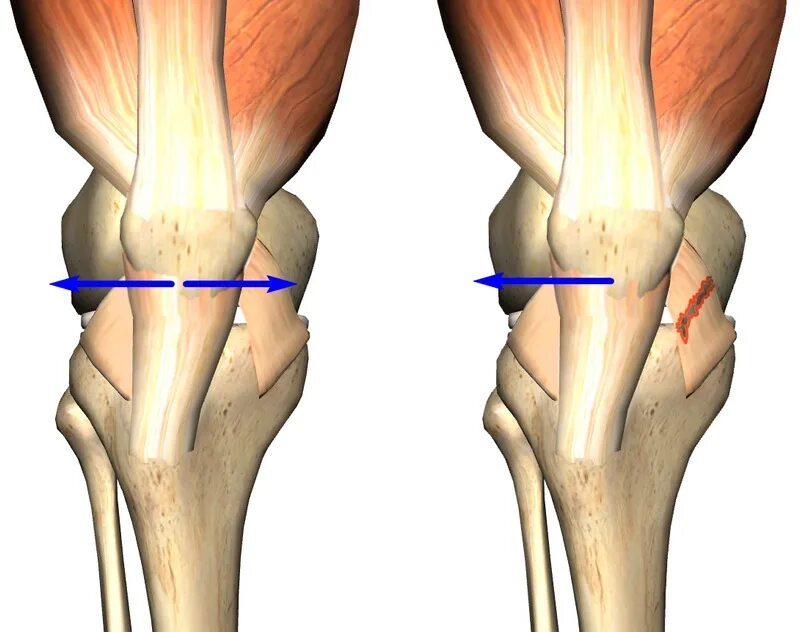

Подвывих сухожилия